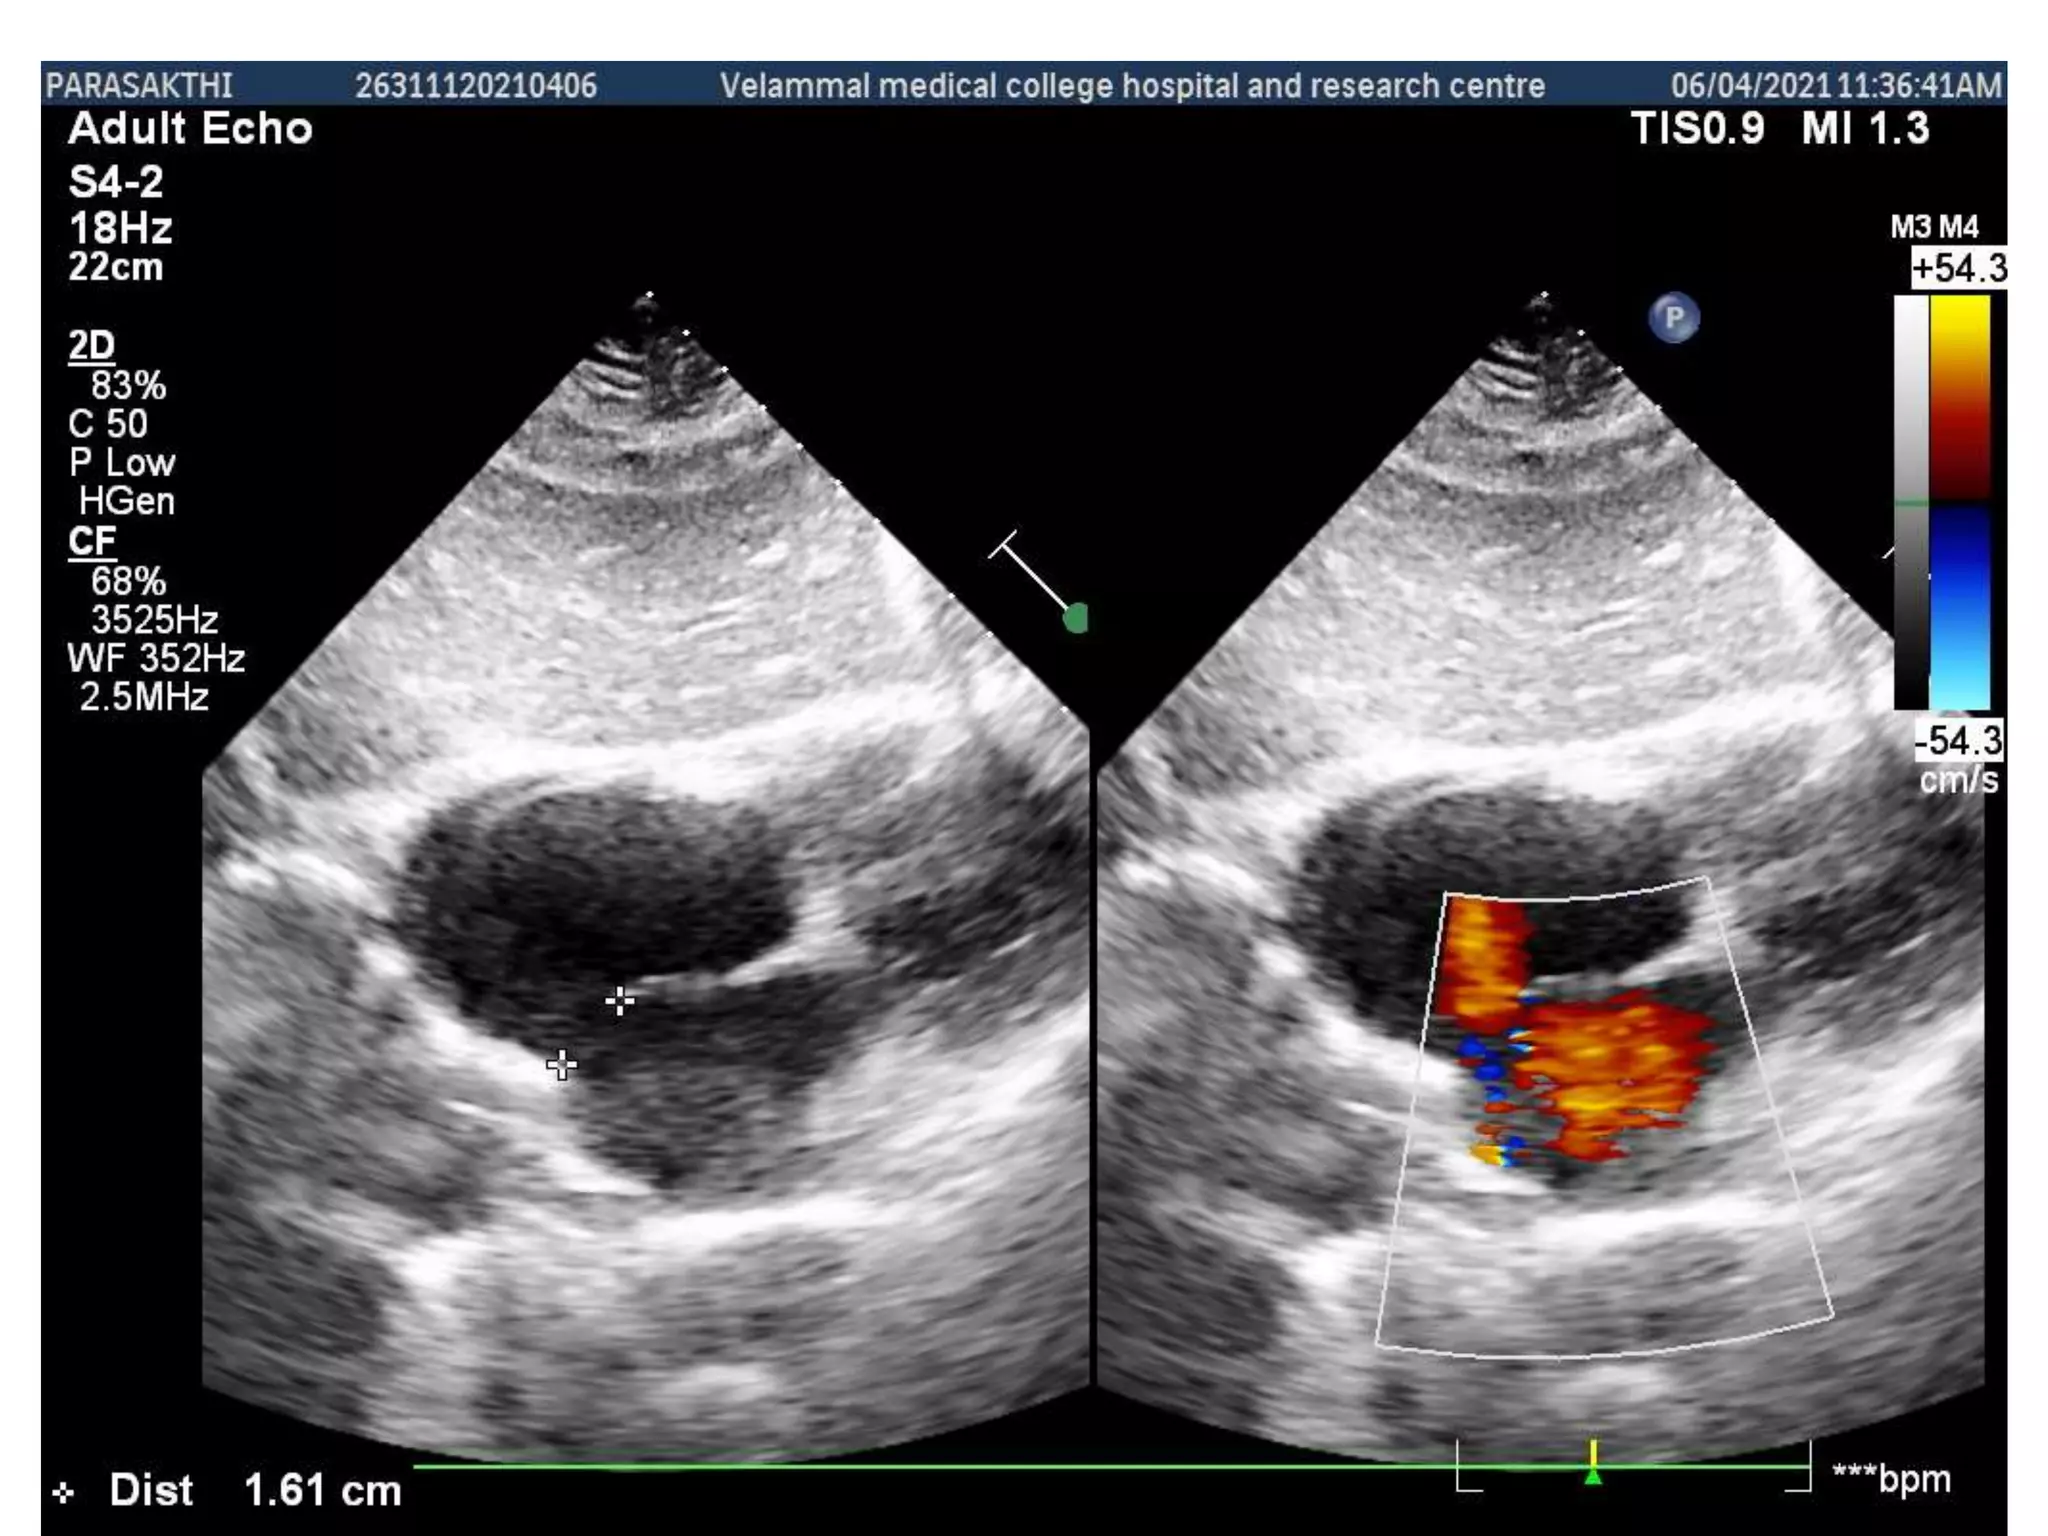

Asd ostium secundum with possible

drop out of interatrial septum

predominant left to right shunt

Color flow showing interartrial septal

defect

ASD and associated flow

ASD and associatedflow • TTE is usually diagnostic for secundum and primum ASDs when a complete examination (including multiple precordial windows) is performed by a trained sonographer/imager, unless the shunt is very small or images are technically suboptimal. • Clues to the presence of a secundum or primum defect include abrupt discontinuity or drop out of the interatrial septum. • Hypermobility of the septum, particularly in association with an abrupt discontinuity, is also suggestive of secundum defect. • TTE may also detect unroofed coronary sinus defects.

• The sizeof an ASD on two-dimensional TTE does not correlate well with shunt flow measured at catheterization. ASD size is better assessed with color flow and pulsed- wave Doppler or three-dimensional TTE or TEE imaging. • The addition of color flow Doppler imaging can help identify or confirm the presence of an ASD and indicate the overall direction of the flow across the atrial septum • Reducing the Nyquist limit (the upper limit of velocity that can be detected with a given Doppler pulse frequency) may enable detection of the turbulent shunt flow.